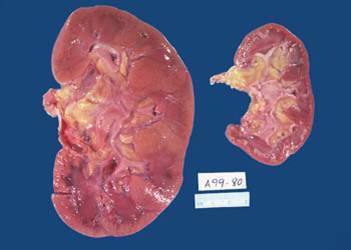

The thyroid pictured on the right has undergone hyperplasia and hypertrophy.

Answer

• True

• False